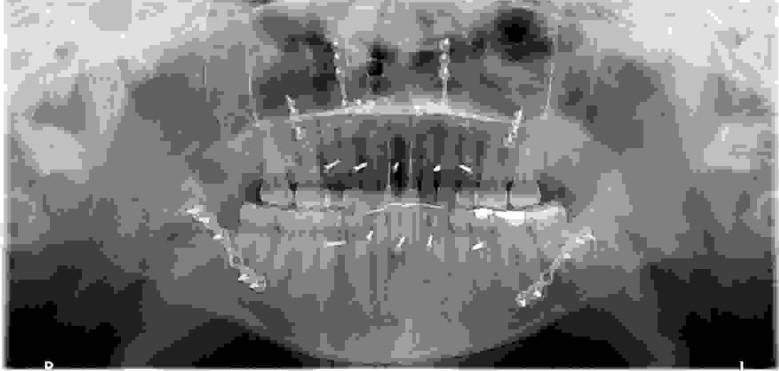

Korektę dysproporcji wielkości szczęki żuchwy można przeprowadzić na wiele sposobów uzależnionych od danej wady rozwojowej. Na podstawie poniższego zdjęcia pantomograficznego wskaż, jaki chirurgiczny zabieg ortognatyczny został wykonany:

Pytanie 72